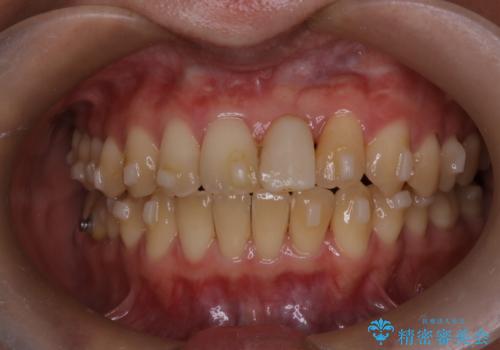

前歯の開咬とシザーズバイトを改善|インビザライン矯正

- 治療計画

前歯が噛まないため咀嚼が困難で、シザーズバイトにより噛み合わせに不調を感じていました。インビザラインを用いて、透明なマウスピースによる目立ちにくい矯正治療を実施。奥歯のシザーズバイトを改善した後、前歯の歯列を緻密に調整し、噛み合わせを整えました。定期的なマウスピース交換を通じて徐々に歯列が改善され、治療終了後には前歯が正常に咬合するようになり、噛み合わせの機能性と審美性が共に向上しました。